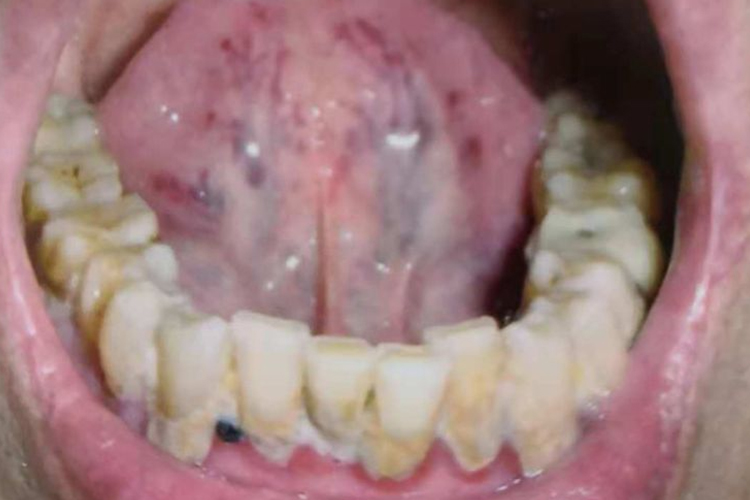

舌下络脉曲张:表现为舌下络脉静脉干饱满、隆起,直径大于2.7mm,伴有迂曲,甚至成囊柱状或串珠状;

舌下络脉瘀点:表现为舌下络脉出现暗红或紫褐色点状凸起或蓝色丘疹样改变;

舌下络脉淤丝:表现为舌下或外侧带边缘呈青紫色丝条状或丝网状改变。